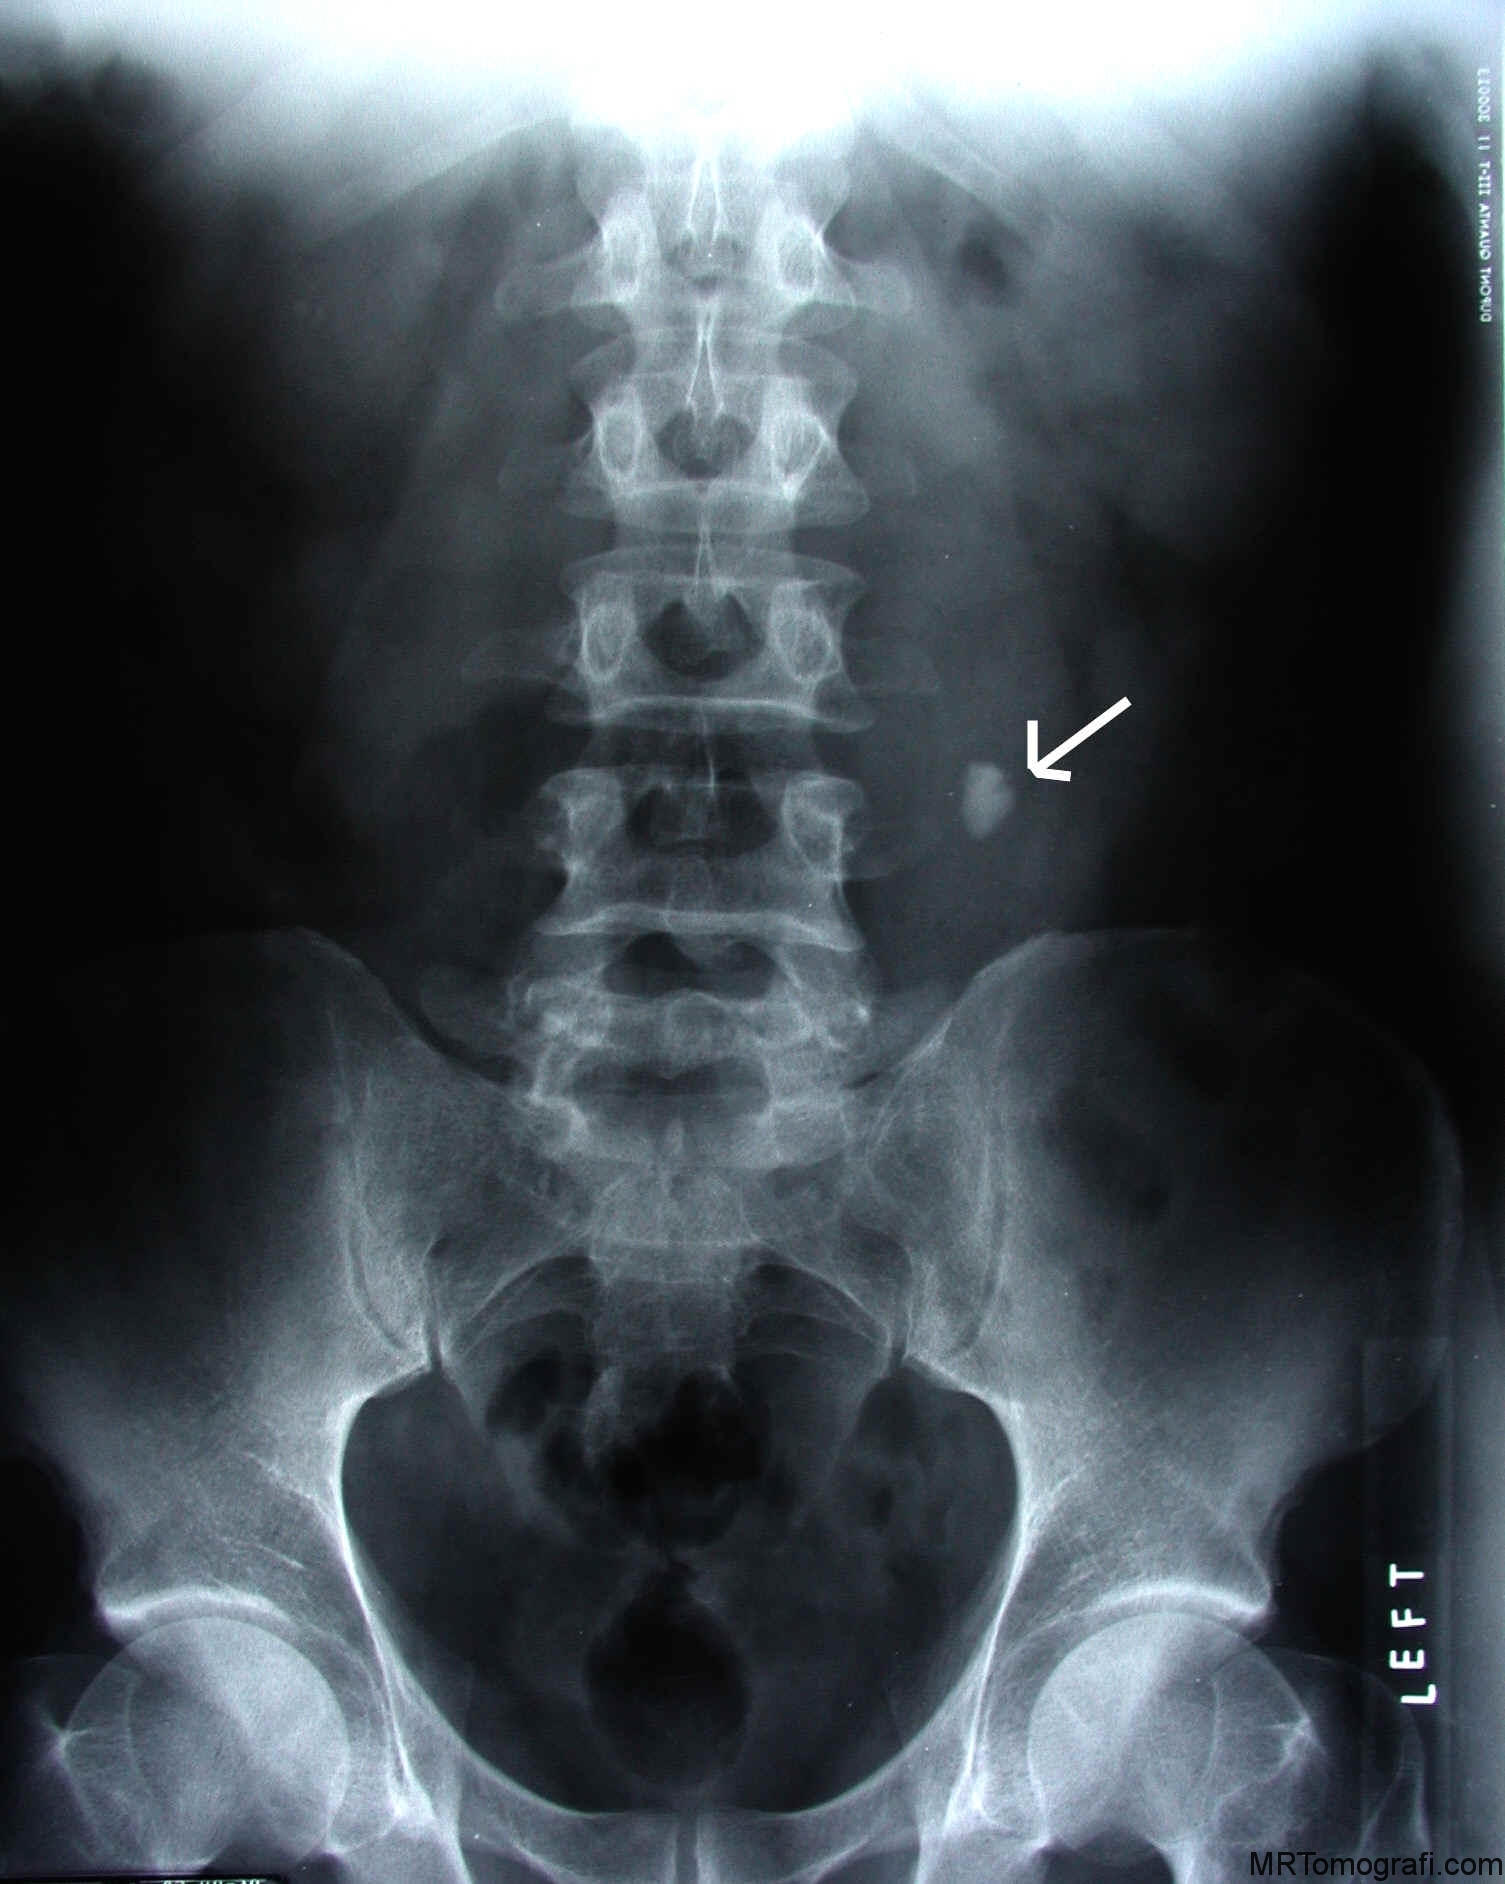

Конкременты почек кт

Конкременты почек кт 104 фотографий